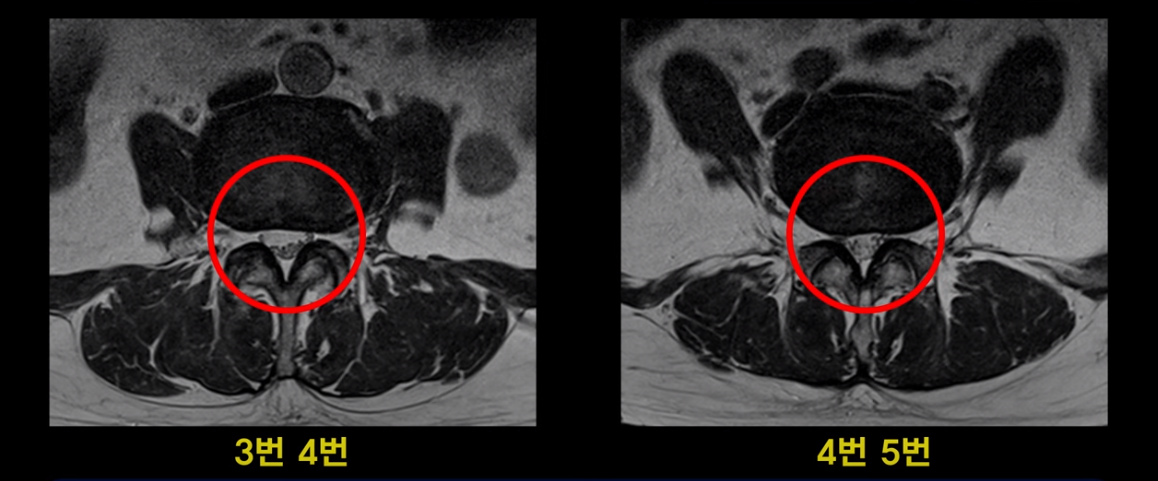

이분 MRI를 보면 여러 마디가 퇴행이 진행되어 있고

3번 4번과 4번 5번에 중심성 협착이 있는데

4번 5번이 더 심합니다.

또 4번 5번 마디에 오른쪽으로 찢어져서 밀려나온 디스크 탈출이 보입니다.

밀려나온 수핵이 조금 흘러내려 있습니다.